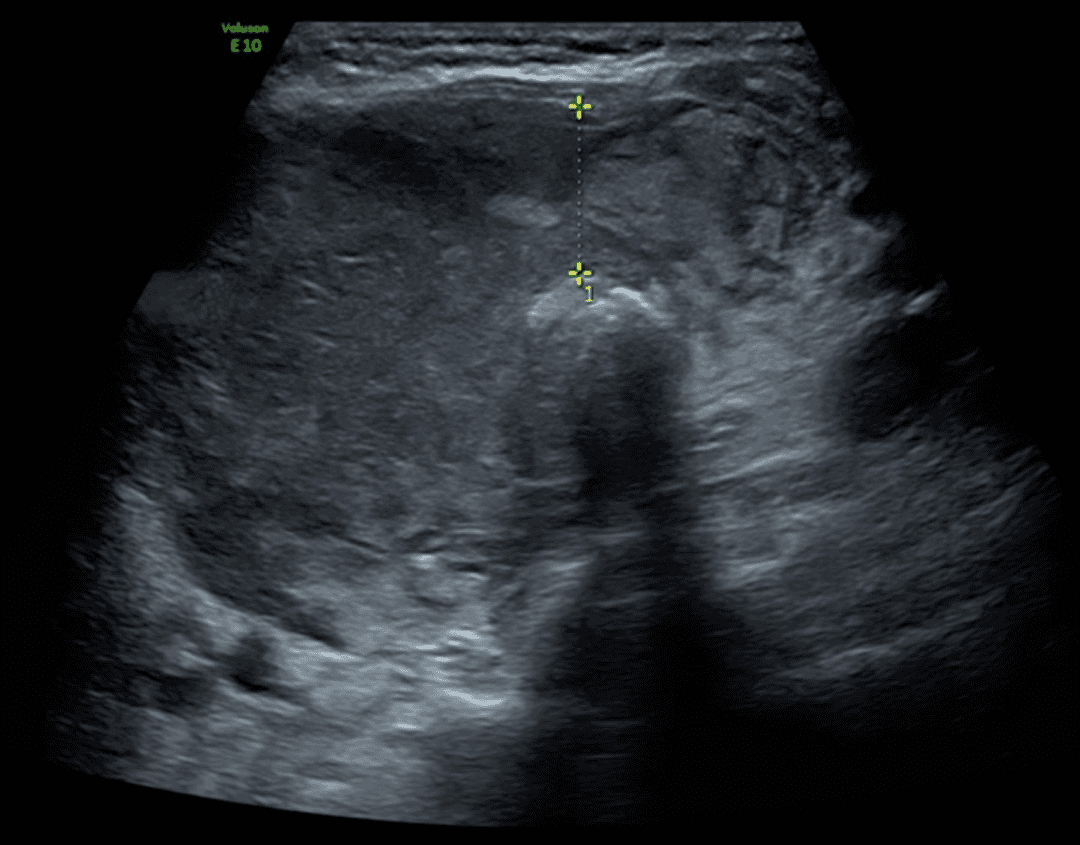

El linfoma tiroideo suele aparecer sobre una base previa de Hashimoto y puede manifestarse como una masa muy hipoecogénica, lobulada y con vascularidad anómala. El carcinoma anaplásico, por su parte, representa el extremo de agresividad: masa mal delimitada, infiltración de músculos y vasos cervicales, desplazamiento o compromiso de la vía aérea y progresión clínica acelerada. En ambos casos, la ecografía cumple una función crítica de sospecha temprana, pero la valoración de extensión local con TC o RM adquiere protagonismo inmediato. De forma similar, un bocio pétreo, indoloro y de crecimiento rápido debe abrir la posibilidad de tiroiditis de Riedel o malignidad infiltrativa.

Cuando el tiroides pierde su arquitectura habitual y se transforma en una masa hipoecogénica dominante, el ultrasonido deja de hablar de inflamación y empieza a sugerir agresividad biológica. En el linfoma tiroideo, el valor diagnóstico está en reconocer una lesión expansiva, de crecimiento rápido y alto efecto local, a menudo sobre una glándula previamente afectada por Hashimoto. La clave para el radiólogo no es solo describir la masa, sino identificar a tiempo que esta morfología exige una ruta diagnóstica urgente.